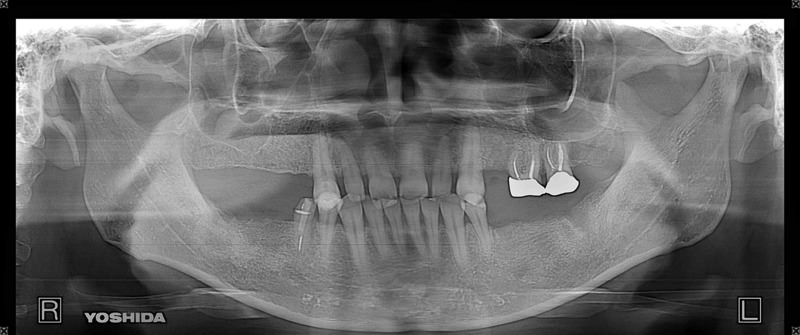

症例140代 男性 主訴 奥歯に歯を入れたい、しっかり噛みたい

治療前

治療後(5年経過)

主訴 奥歯がない為、食事が不自由である。入れ歯は煩わしいので、固定制のインプラントにして欲しいと訴え来院。口腔内全体で6本のインプラントを埋入。仮歯にて神経筋機構、顎関節のバランスを整え、リハビリを経て、約5ヶ月後にジルコニアを装着。

リスクとしては、外科的侵襲がある。デメリットは、保険外診療の為、経済的負担がある。

費用 316万(税込) (オペ・仮歯・最終補綴物まで含む)